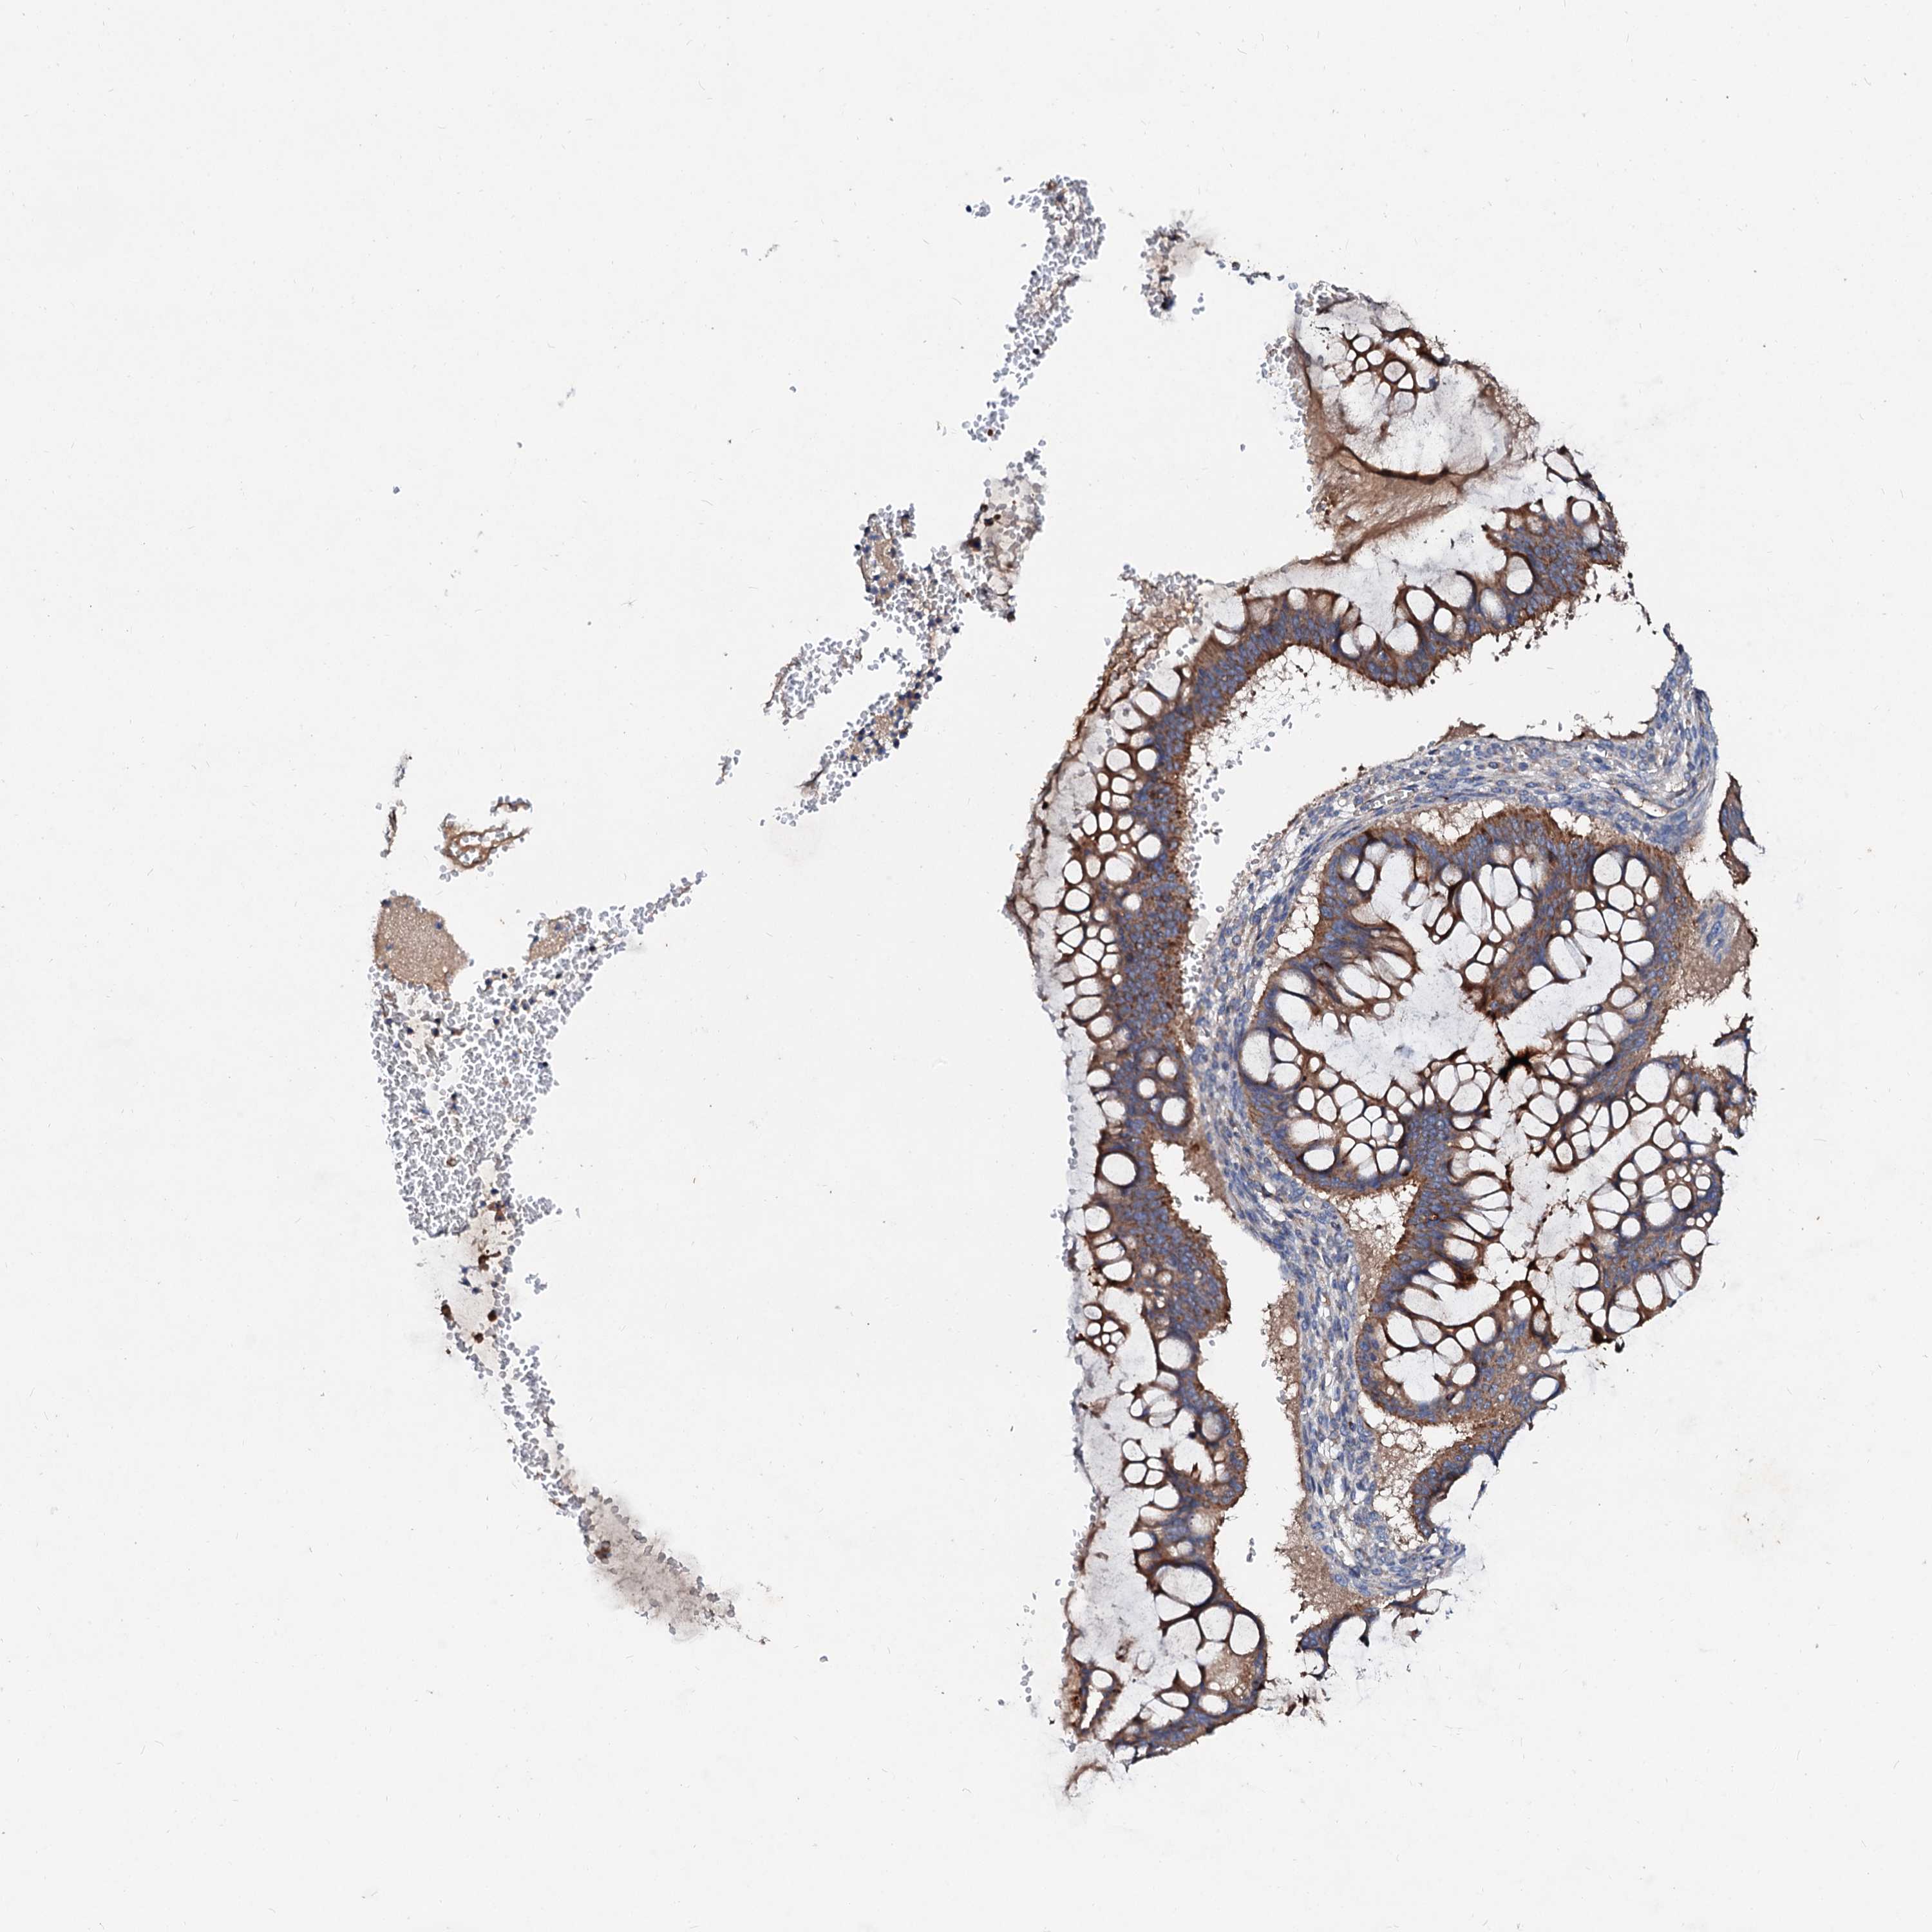

OVARIAN CANCER - Protein expressioni

A mouse-over function shows sample information and annotation data. Click on an image to view it in a full screen mode. Samples can be filtered based on level of antibody staining by selecting one or several of the following categories: high, medium, low and not detected. The assay and annotation is described here.

Note that samples used for immunohistochemistry by the Human Protein Atlas do not correspond to samples in the TCGA dataset.

Antibody stainingi

Antibody staining in the annotated cell types in the current human tissue is reported as not detected, low, medium, or high, based on conventional immunohistochemistry profiling in selected tissues. This score is based on the combination of the staining intensity and fraction of stained cells.

Each image is clickable and will lead to virtual microscopy that enables deeper exploration of all samples and also displays staining intensity scores, fraction scores and subcellular localization as well as patient and tissue information for each sample.

Antibody HPA040120

Staining

High

Medium

Low

Not detected

Intensity

Strong

Moderate

Weak

Negative

Quantity

>75%

75%-25%

<25%

None

Location

Nuclear

Cytoplasmic/membranous

Cytoplasmic/membranous,nuclear

Cystadenocarcinoma, serous, NOS

Carcinoma, endometroid

Cystadenocarcinoma, mucinous, NOS

Carcinoma, NOS